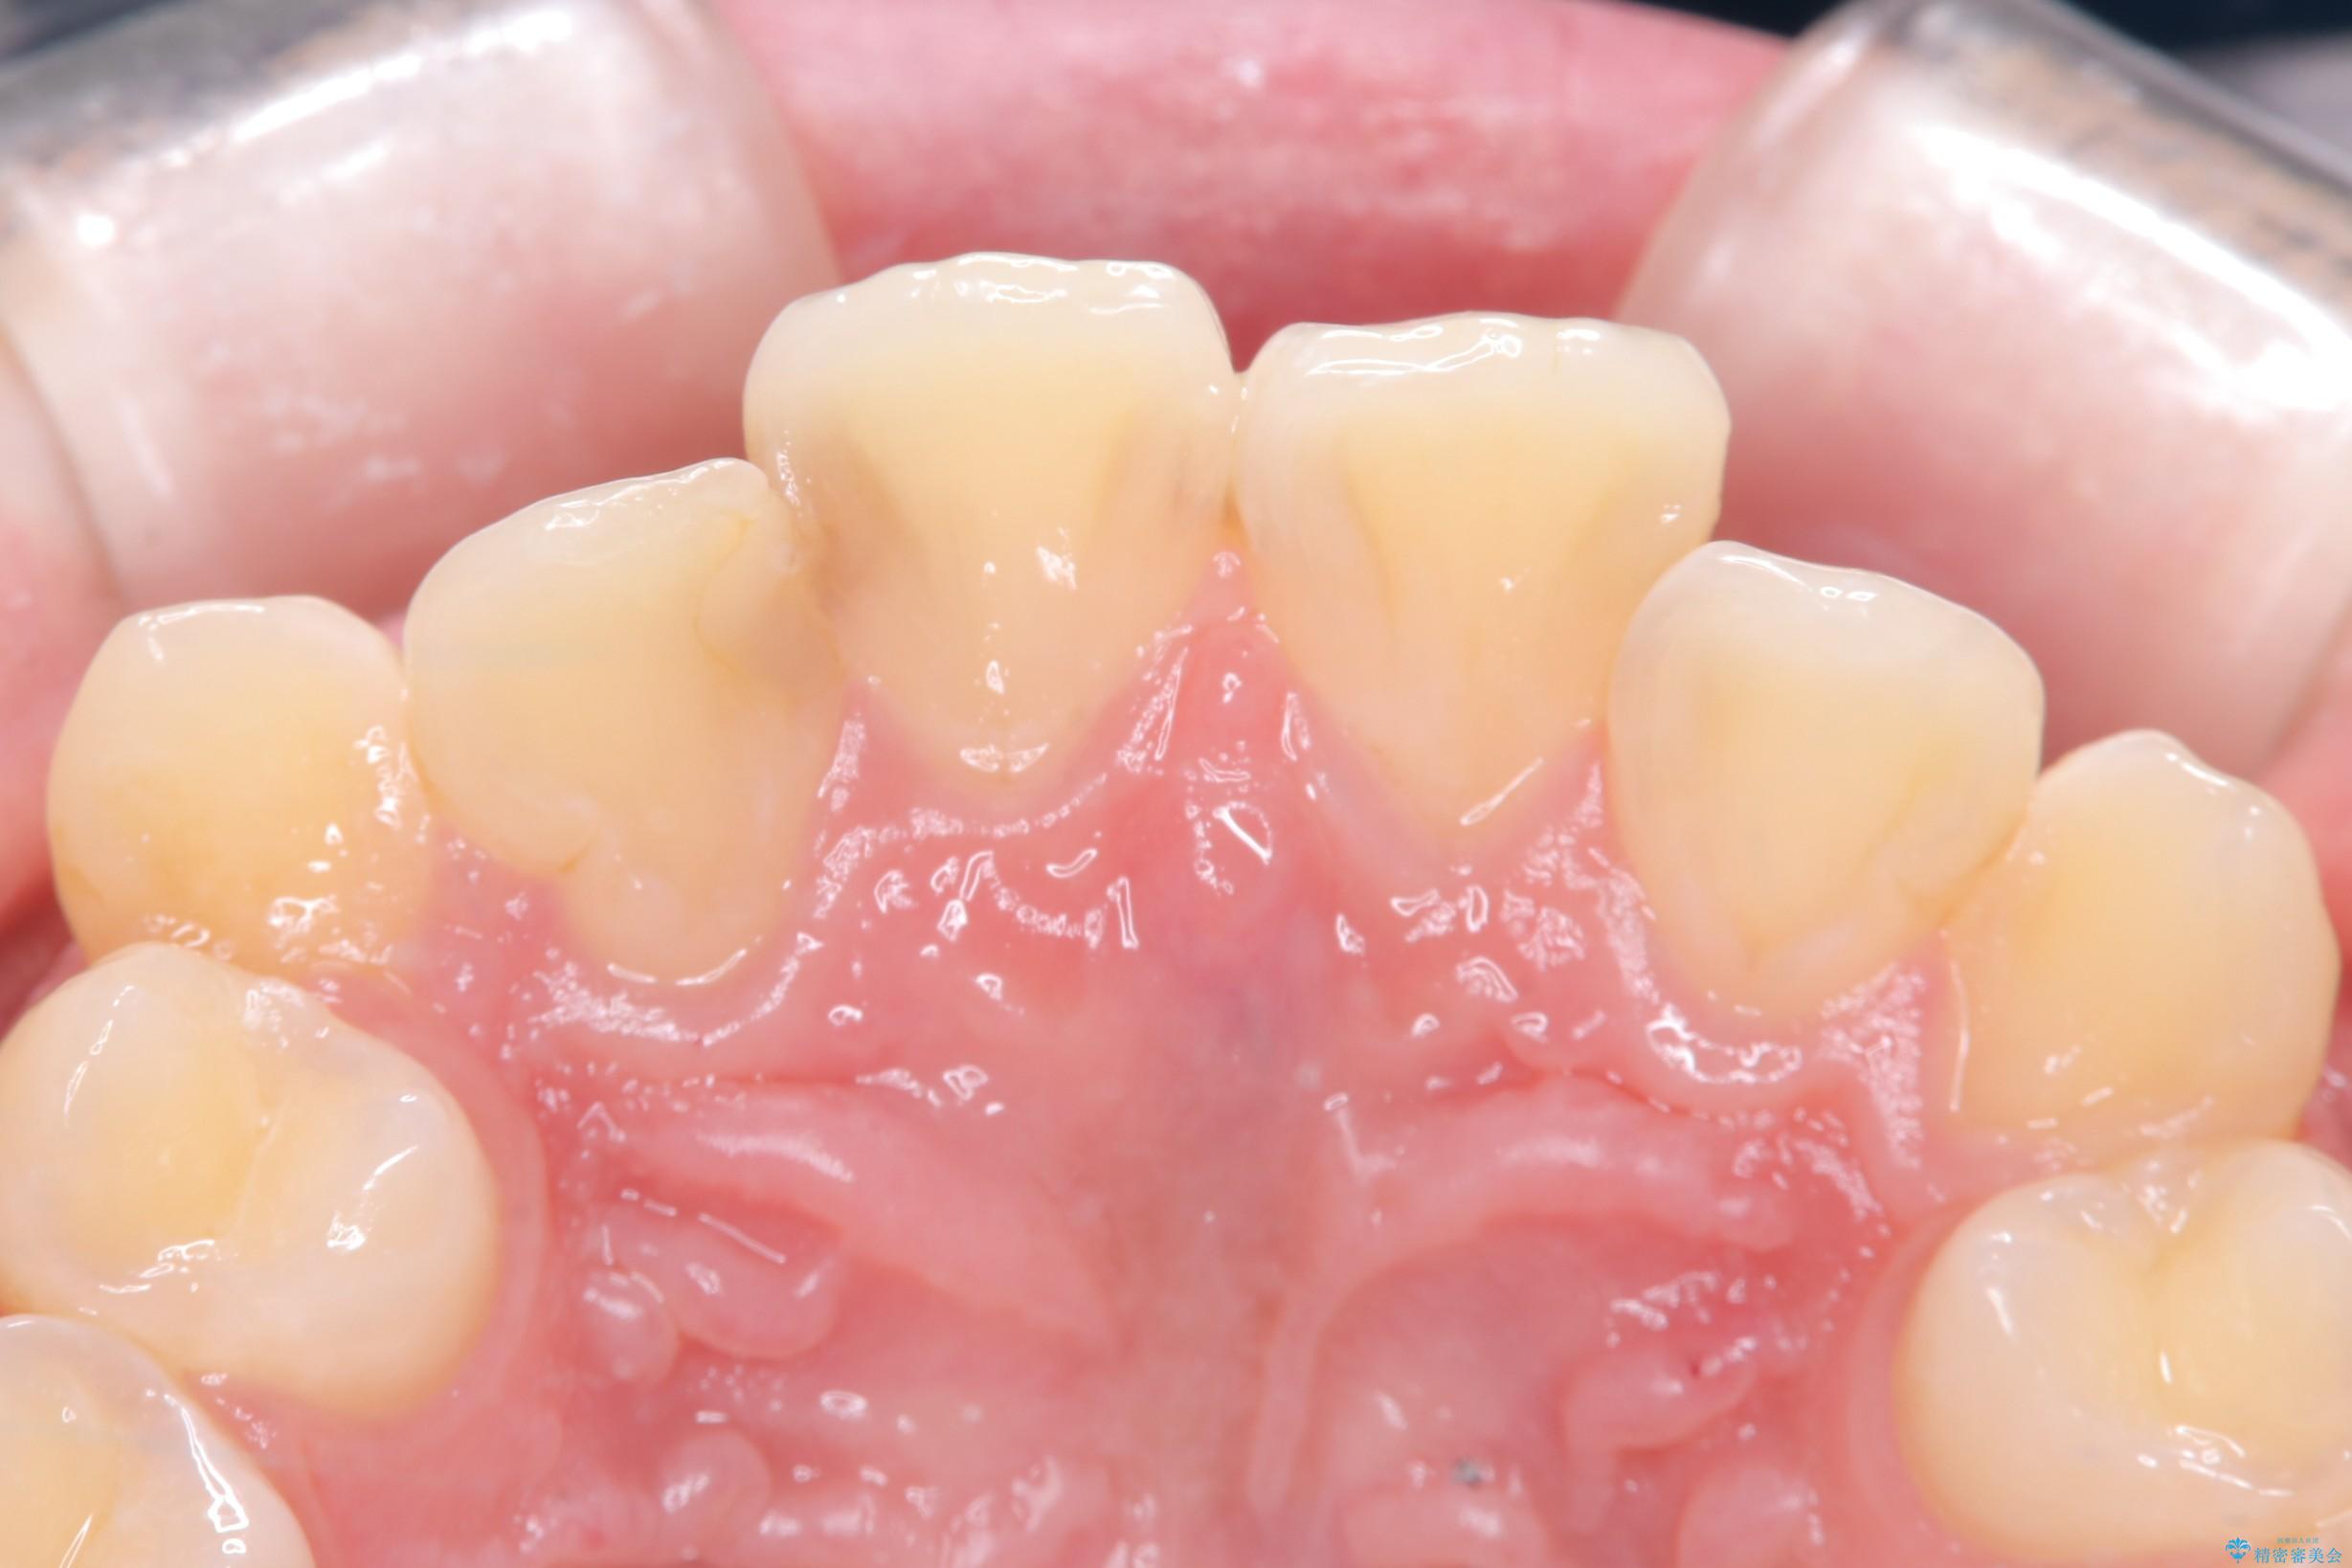

右上2番の歯に自発痛を認め、症状や歯髄診・レントゲン像から不可逆性歯髄炎と診断し、精密根管治療から歯冠補綴まで行うこととなりました。

初診時に歯髄診断を行い、不可逆性歯髄炎と診断し抜髄から補綴修復までの流れを説明し、精密根管治療、ファイバ-コア築造、オールセラミッククラウン(St)修復を行うこととしました。